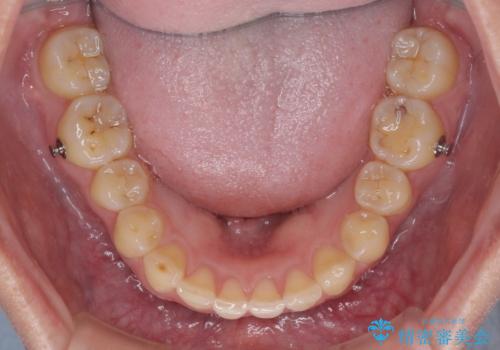

- 食いしばりが気になっていたとのことで来院された患者様です。

当初は睡眠時のマウスピースのみの製作をご希望でしたが、矯正治療の提案をしたところ、インビザラインにて矯正治療を行うこととなりました。

矯正治療中に食いしばりがより強くなることがあるため、半年に1回のペースでボツリヌストキシンによる咬合力緩和を並行して行うこととしました。

咬合力の緩和と食いしばりがちな咬み合わせが改善され、顎の負担が大幅に軽減されました。